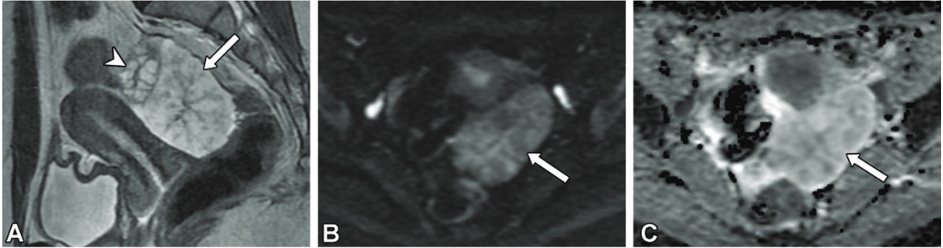

MRI:

両側卵巣に嚢胞構造(T2WI高信号、T1WI軽度低信号)

骨盤底部、右付属器表面に付着する腫瘤

明瞭なT2WI高信号、T1WI低信号、DWI高信号、ADC高値

右卵巣表面に連なるT2WI低信号の樹枝状構造

樹枝状構造は造影され、腫瘤本体は造影効果が弱い

少量の腹水と軽度腹膜肥厚